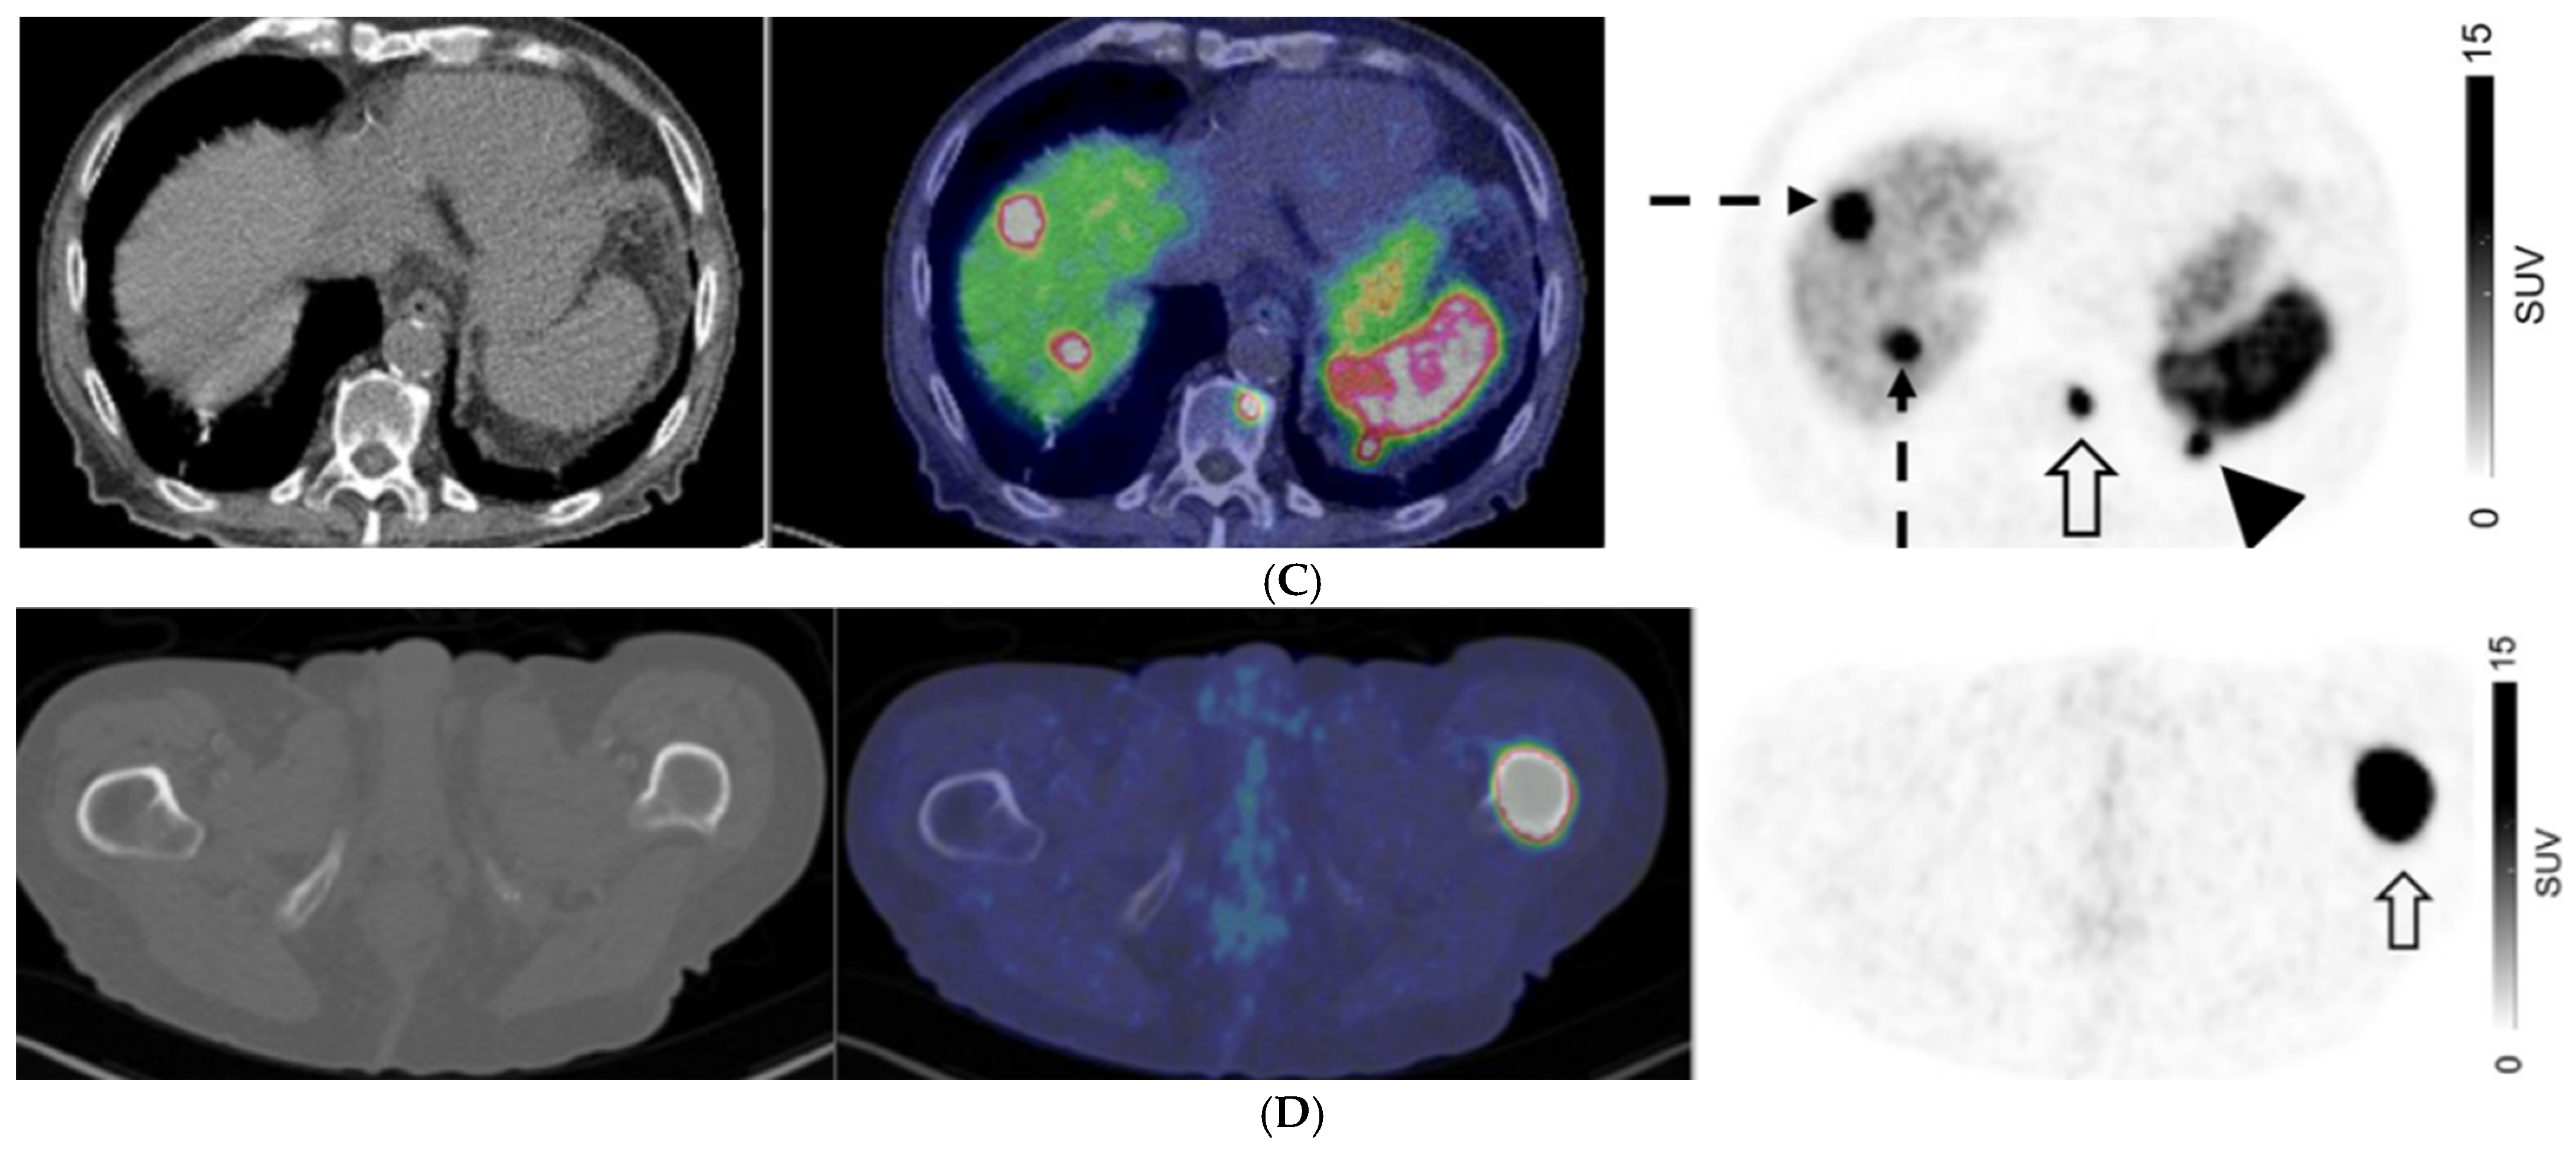

A 67-year-old man with well-differentiated G1 small bowel NET, Ki 67 = 3% metastatic to liver. Staging CT showed mid-ileal tumor, regional nodal metastases, and bilobar liver metastases [CT stage: n1M1a]. 68Ga-DOTATATE PET/CT (A,B) Axial and Coronal—CT (left), fused PET/CT (middle) and PET (right); (C) Sagittal—Fused PET/CT (left) and PET (right) shows in addition, extrahepatic metastases including extraregional nodes including supraclavicular and cardiophrenic nodes (arrows in (A,C)), and peritoneal metastases (dotted arrows in (B,C)); overall, PET stage: n1M1c.

Figure 3.

A 76-year-old man with well-differentiated G3 pancreatic neuroendocrine tumor (SUVmax 131.5, Krenning score 4), with bilobar liver metastases on CT. 68Ga-DOTATATE PET (A) MIP image; (B–D) Axial images: CT (left), fused PET/CT (middle), and PET (right). PET shows an intensely-avid locally advanced pancreatic tail mass (SUVmax = 132; solid arrow in (B)), liver metastases (biopsy proven; dotted arrows in (B,C)), peritoneal deposit (arrowhead in (C)) and bone metastases (open arrows in (C,D)).

For patients with GEP NETs, no distant metastases (M0) were observed on both CI and PET in 186/369 (50.4%) of patients. There were 83 patients with GEP NETs who had discordant M-stage on CI and PET, in which PET suggested a higher stage in 75/83 patients (90.4%) and lower stage in 8/83 (9.6%) (Figure 2). For those with GEP NETs, extrahepatic metastatic disease was identified by PET in 42/114 (36.8%) patients where CI showed only liver metastases (M1a) (Figure 3).